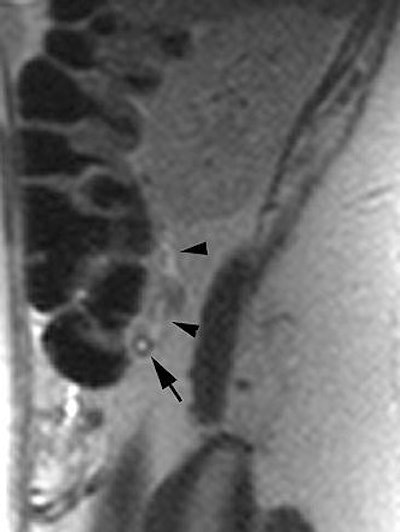

| Parameters | Coronal SSFSE | Axial 2D FS SSFSE | 2D TOF |

| Echo time (msec) | 60 | 60 | 100 |

| Flip angle (degrees) | 130-155 | 130-155 | 45 |

| Section thickness (mm) | 4 | 4 | 3 |

| Gap (mm) | 1 | 1 | 1 |

| Field-of-view (mm) | 350 | 350 | 350 |

| Bandwidth (kHz)** | 62.5 | 62.5 | 31.25 |

| Breath-hold | Yes | Yes | Yes |

| *FS = fat-saturated, TOF = time of flight **62.5 kHz = 488 Hz/pixel, 31.25 kHz = 244 Hz/pixel |

| Adapted from table 2, Pedrosa I, Zeikus EA, Levine D, et al. "MR Imaging of Acute Right Lower Quadrant Pain in Pregnant and Nonpregnant Patients." Radiographics 2007; 27:721-753. | |||